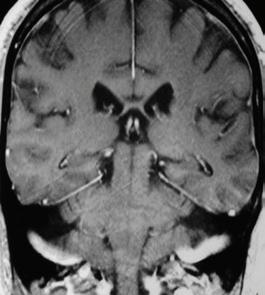

University of Freiburg, Germany

• Dr. Deepak Venkateshvaran

University of Cambridge, United Kingdom

• Stanislas Rohart

CNRS/Université Paris-Saclay, France

• Dr. Tobias Cramer